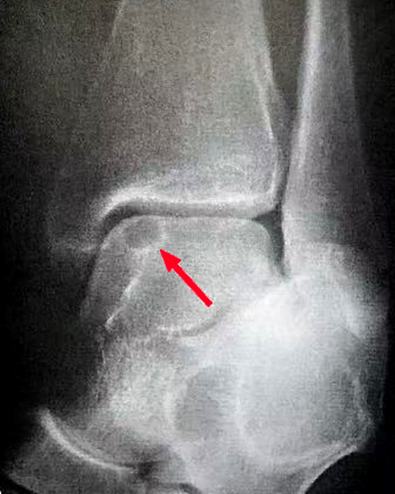

图1:距骨软骨损伤

图2:影像学分型(CT):I型,距骨顶部软骨下骨囊变,距骨顶部完整;Ⅱ型,软骨下骨囊变通入关节腔;Ⅲ型,软骨下骨骨折且无骨块移位;IV型,软骨下骨骨折且有骨块移位